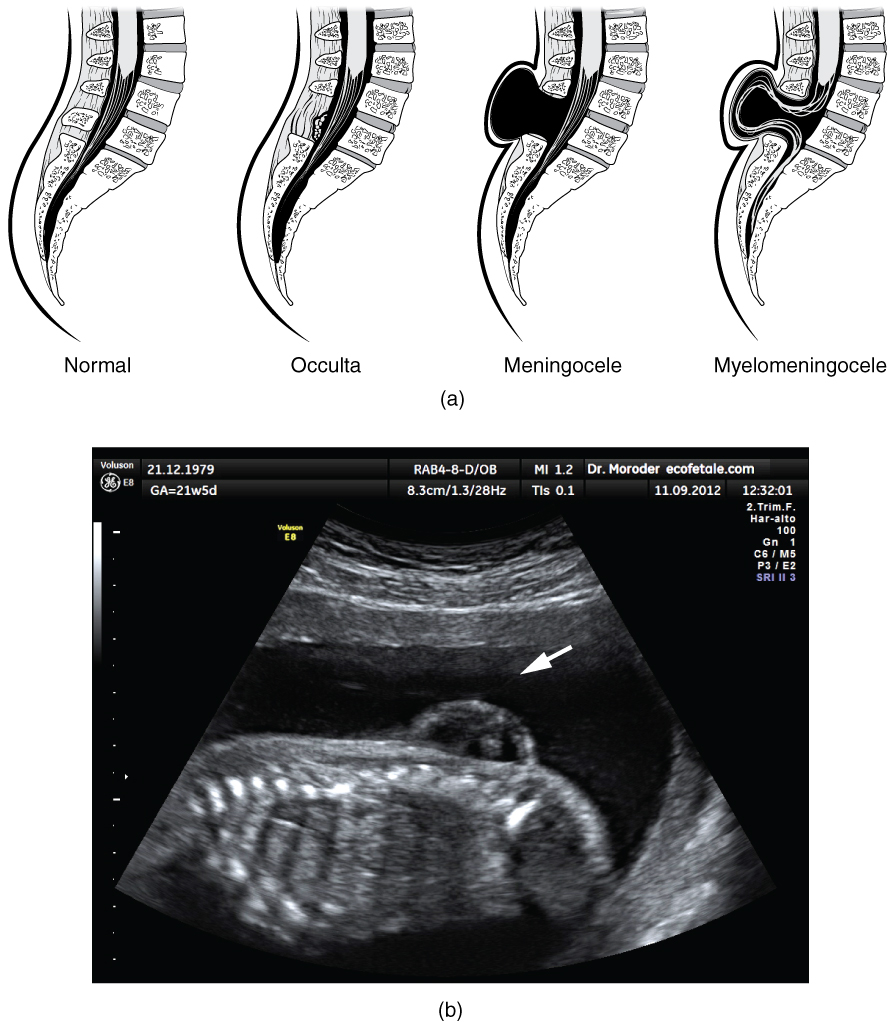

Early formation of the nervous system depends on the formation of the neural tube. A groove forms along the dorsal surface of the embryo, which becomes deeper until its edges meet and close off to form the tube. If this fails to happen, especially in the posterior region where the spinal cord forms, a developmental defect called spina bifida occurs. The closing of the neural tube is important for more than just the proper formation of the nervous system. The surrounding tissues are dependent on the correct development of the tube. The connective tissues surrounding the CNS can be involved as well.

There are three classes of this disorder: occulta, meningocele, and myelomeningocele (Figure 14.1.4). The first type, spina bifida occulta, is the mildest because the vertebral bones do not fully surround the spinal cord, but the spinal cord itself is not affected. No functional differences may be noticed, which is what the word occulta means; it is hidden spina bifida. The other two types both involve the formation of a cyst—a fluid-filled sac of the connective tissues that cover the spinal cord called the meninges. “Meningocele” means that the meninges protrude through the spinal column but nerves may not be involved and few symptoms are present, though complications may arise later in life. “Myelomeningocele” means that the meninges protrude and spinal nerves are involved, and therefore severe neurological symptoms can be present.

Often surgery to close the opening or to remove the cyst is necessary. The earlier that surgery can be performed, the better the chances of controlling or limiting further damage or infection at the opening. For many children with meningocele, surgery will alleviate the pain, although they may experience some functional loss. Because the myelomeningocele form of spina bifida involves more extensive damage to the nervous tissue, neurological damage may persist, but symptoms can often be handled. Complications of the spinal cord may present later in life, but overall life expectancy is not reduced.

This figure shows the spinal cord in spina bifida, a birth defect. In the top panel, four different spinal cords are shown. The leftmost panel shows a normal spinal cord. The remaining panels show the spinal cord in various stages of spina bifida. The bottom panel shows an ultrasound image, with a white arrow showing the region of the defect.

Figure 14.1.4 – Spinal Bifida: (a) Spina bifida is a birth defect of the spinal cord caused when the neural tube does not completely close, but the rest of development continues. The result is the emergence of meninges and neural tissue through the vertebral column. (b) Fetal myelomeningocele is evident in this ultrasound taken at 21 weeks.